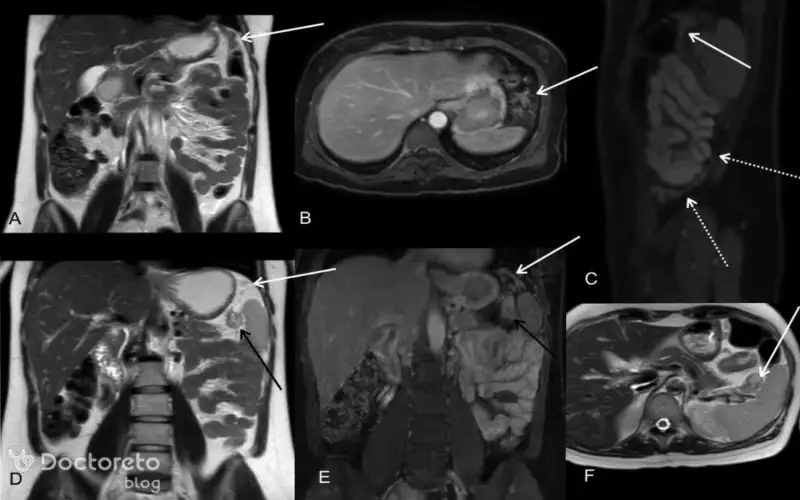

عکس سرطان معده بدخیم در مراحل پیشرفته

در این بخش، تصویری از سرطان معده بدخیم در مراحل پیشرفته را نشان دادهایم. در چنین شرایطی تومور علاوه بر معده، ارگانهای مجاور مانند کبد، ریه و استخوان یا اندامهای دیگر را هم درگیر کرده است. در این مرحله، درمان چالشبرانگیزتر شده و پیشبینی روند بیماری دشوارتر است.

عکس تصویربرداری های سرطان معده بدخیم

تصویربرداریهای پزشکی شامل سی تی اسکن، اندوسکوپی به همراه بیوپسی سرطان معده بدخیم میشود. این تصاویر به پزشکان کمک میکنند تا اندازه تومور، نفوذ به لایههای معده و احتمال گسترش آن به ارگانهای دیگر را ارزیابی کنند. با تشخیص قطعی به کمک بیوپسی و نقش تصویربرداری در مرحلهبندی، مسیر درمانی مؤثرتر و تصمیمگیری بهتر پزشک را ممکن میسازد.